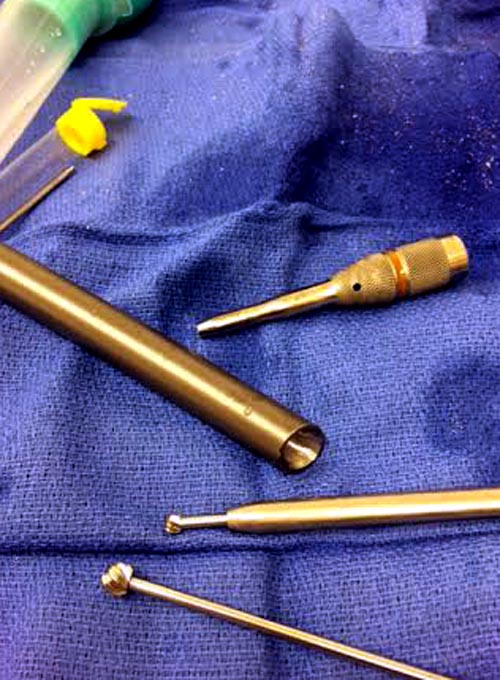

Наши операционные оснащены разными сверхскоростными алмазными и другими

режущими инструментами типа Midas Rex. Но моя двухдневная ручная работа

не дала результатов, и выемка для протеза получился неглубокой. Помогла

смекалка, за бутылку наш русский токарь исправил глубину за пять минут.

Гвоздь из ретроградного гвоздя DePuy в 15 мм получился немного тоньше,

чем у Российских коллег.

Операция не обошлась без казуса, при подготовке гвоздя произошла ошибка

в расчете. Пришлось коррегигировать по ходу операции, где длинный

дистальный отдел гвоздя срезали во время операции.